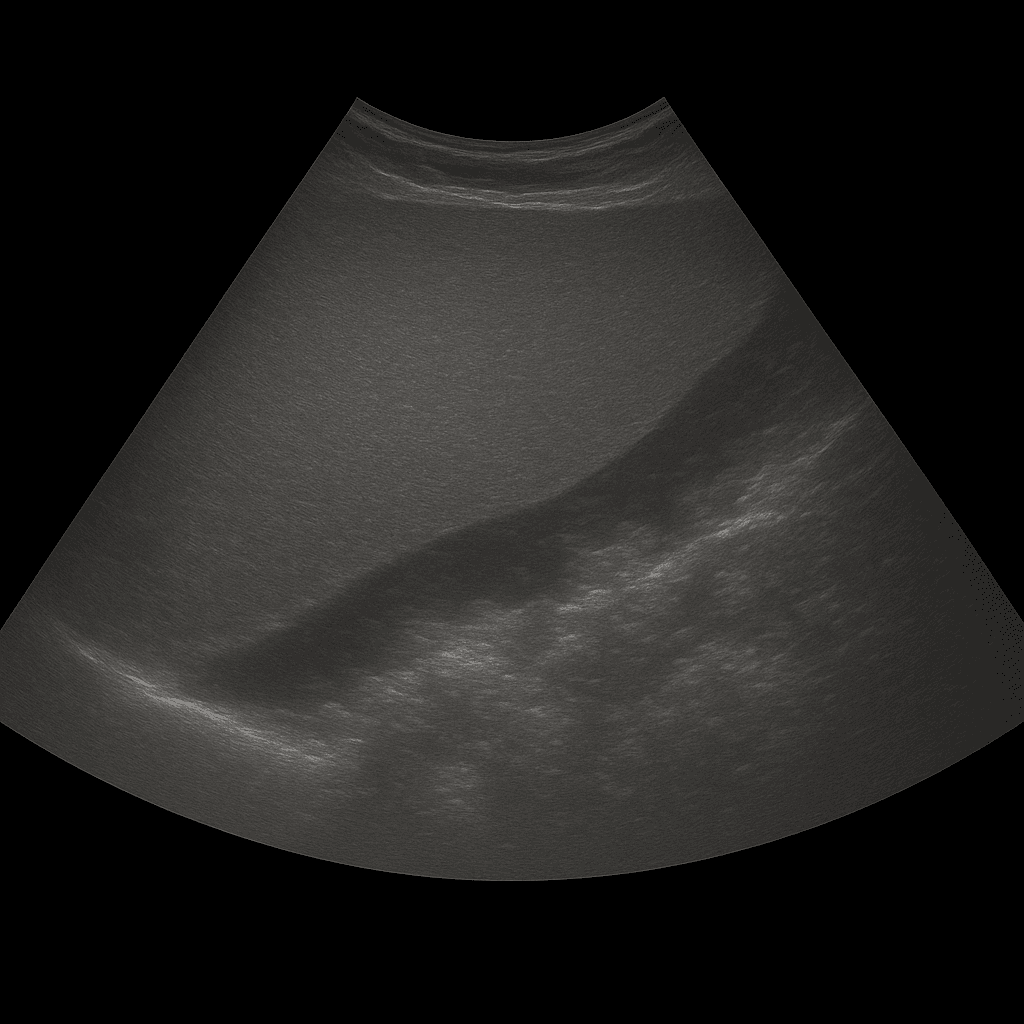

Ultraljud av lever med elastografi är en mer avancerad undersökning som mäter levervävnadens styvhet för att bedöma graden av fibros eller ärrbildning i levern. Till skillnad från en vanlig ultraljudsundersökning, som främst visar leverns struktur och utseende, kan elastografi kvantifiera hur hård eller mjuk vävnaden är – vilket gör det möjligt att tidigt upptäcka tecken på leversjukdom innan förändringarna syns på bild.

Metoden är ett skonsamt alternativ till leverbiopsi och ger en objektiv mätning av leverns elasticitet. Genom att mäta hur snabbt mekaniska vågor rör sig genom vävnaden kan läkaren avgöra hur stel levern är – ju styvare vävnad, desto mer fibros.